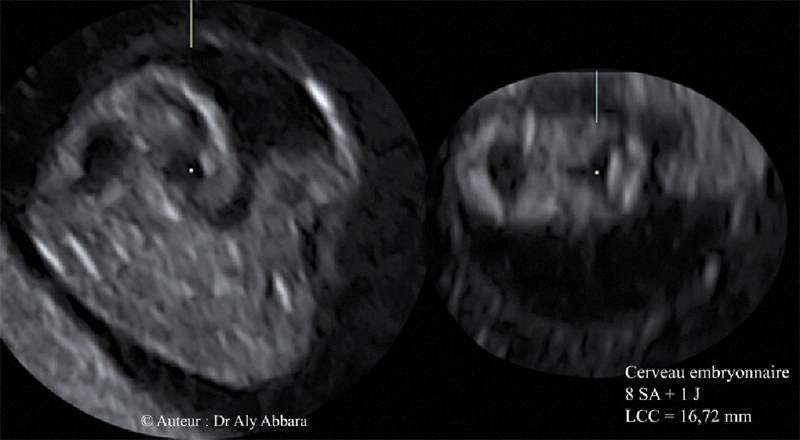

Cerveau embryonnaire - embryon âgé de 8 SA + 1 jours

(LCC = 16,72 mm)

Coupe sagittale médiane :

Analyse des éléments formant de l'ensemble du cerveau à cet âge embryonnaire : le prosencéphale se divisant en deux télencéphales occupés (chacun) partiellement par son ventricule latéral dérivé de la vésicule prosencéphalique dont la partie centrale constituera le 3° ventricule ; ce dernier se placera au centre du diencéphale (entre les deux futurs thalamus) ; le mésencéphale et sa vésicule (futur aqueduc cérébral) ; le rhombencéphale ; la courbure mésencéphalique ; la courbure pontique avec la fosse rhombencéphalique en arrière.